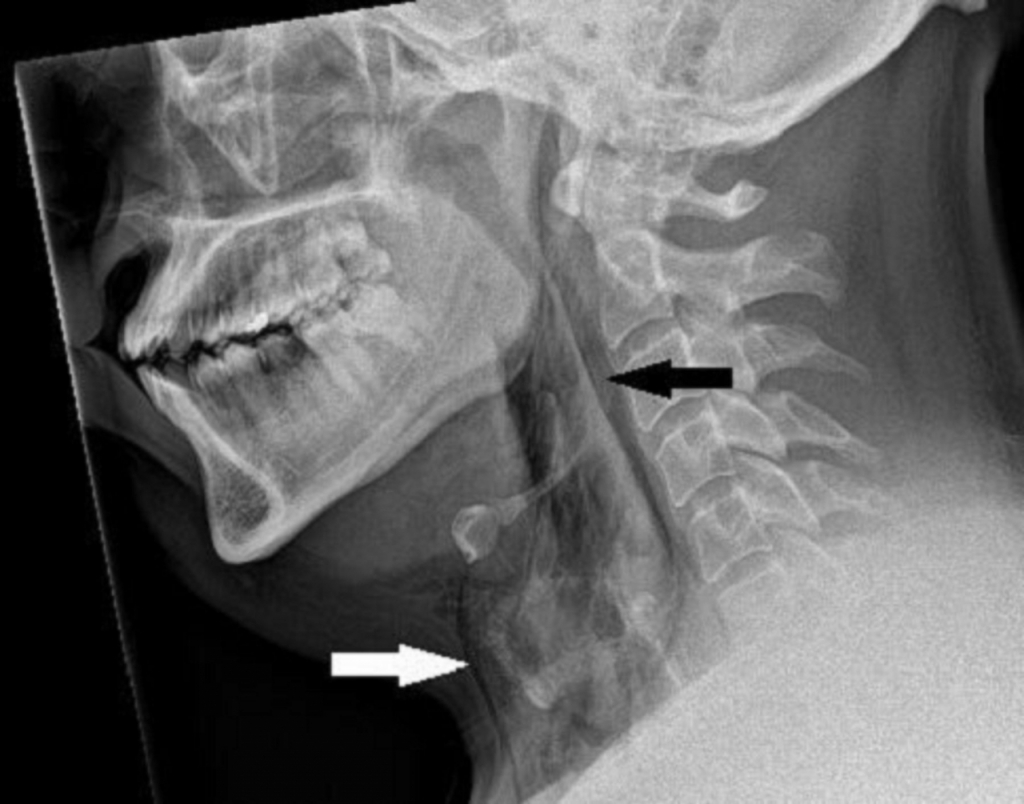

알레르기성 비염을 앓던 30대 스코틀랜드 남성은 자동차를 운전하던 중 재채기가 나왔다. 하지만 재채기가 나오는 시점에 코를 막고 입을 다물었다가 심한 목 통증을 겪었다고 한다. 결국 남성은 응급실로 향했고 정밀 진단을 실시했다.

그 결과 기관지가 찢어져 가로·세로 각 2㎜ 크기 구멍이 생겼다. 일부 폐기종 증상도 나타났다. 폐기종은 기관지나 폐에 염증이 생기고 이로 인해 숨을 쉴 때 폐포가 제 기능을 못하는 질환이다. 만성적 기침이 동반되며 심할 경우 호흡 곤란 증상이 나타난다. 목 통증으로 인해 목의 움직임 범위도 줄어들었다.

연구팀은 "재채기 후 기관지 천공(Perforation·구멍)이 발생한 사례는 이전에 보고된 적이 없다"며 "재채기 중 상부 기도의 압력은 1~2㎪(킬로파스칼) 수준이지만 입과 코를 닫으면 압력이 최대 20배까지 증가할 수 있다"고 밝혔다.